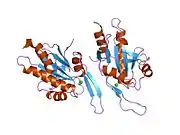

SCO1 is located on the p arm of chromosome 17 in position 13.1 and has 6 exons.[6] The SCO1 gene produces a 33.8 kDa protein composed of 301 amino acids.[10][11] The protein is a member of the SCO1/2 family. It contains 3 copper metal binding sites at positions 169, 173, and 260, a transit peptide, a 25 amino acid topological domain from positions 68–92, a 19 amino acid helical transmembrane domain from positions 93–111, and a 190 amino acid topological domain from positions 112–301 in the mitochondrial intermembrane. Additionally, SCO1 has been predicted to contain 10 beta-strands, 7 helixes, and 2 turns and is a single-pass membrane protein.[8][9]

Mammalian cytochrome c oxidase (COX) catalyzes the transfer of reducing equivalents from cytochrome c to molecular oxygen and pumps protons across the inner mitochondrial membrane. In yeast, 2 related COX assembly genes, SCO1 and SCO2 (synthesis of cytochrome c oxidase), enable subunits 1 and 2 to be incorporated into the holoprotein. This gene is the human homolog to the yeast SCO1 gene.[6] It is predominantly expressed in muscle, heart, and brain tissues, which are also known for their high rates of oxidative phosphorylation.[5] SCO1 is a copper metallochaperone that is located in the inner mitochondrial membrane and is important for the maturation and stabilization of cytochrome c oxidase subunit II (MT-CO2/COX2). It plays a role in the regulation of copper homeostasis by controlling the localization and abundance of CTR1 and is responsible for the transportation of copper to the Cu(A) site on MT-CO2/COX2.[12][8][9][13]